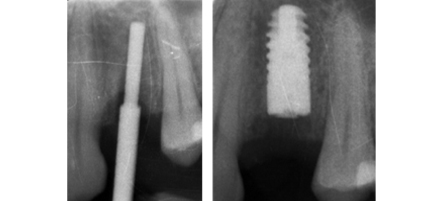

IMPLANT PLACEMENT

Card image Card image Card image Card image Card image Actual Practice Photographs ©Dr.Pavan Bopanna